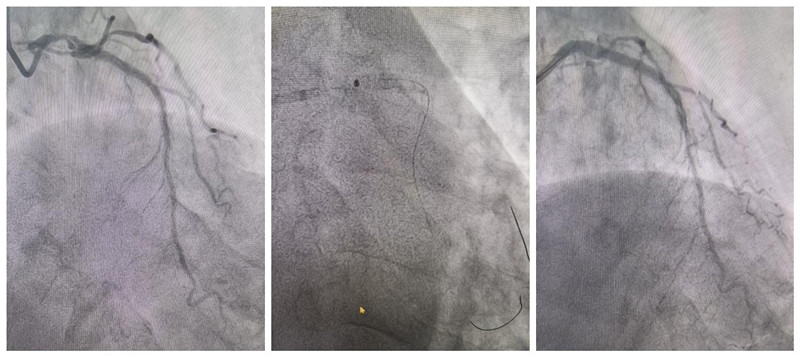

手术于2025年3月12日如期开展。术中,何主任在李杰副主任、李博超主治医师配合下,操作激光导管在支架内严重狭窄病变内反复消蚀成形,最终成功开通支架内严重狭窄,为陈爷爷顺利植入支架。

(术前造影) (术中激光消蚀) (术后造影)